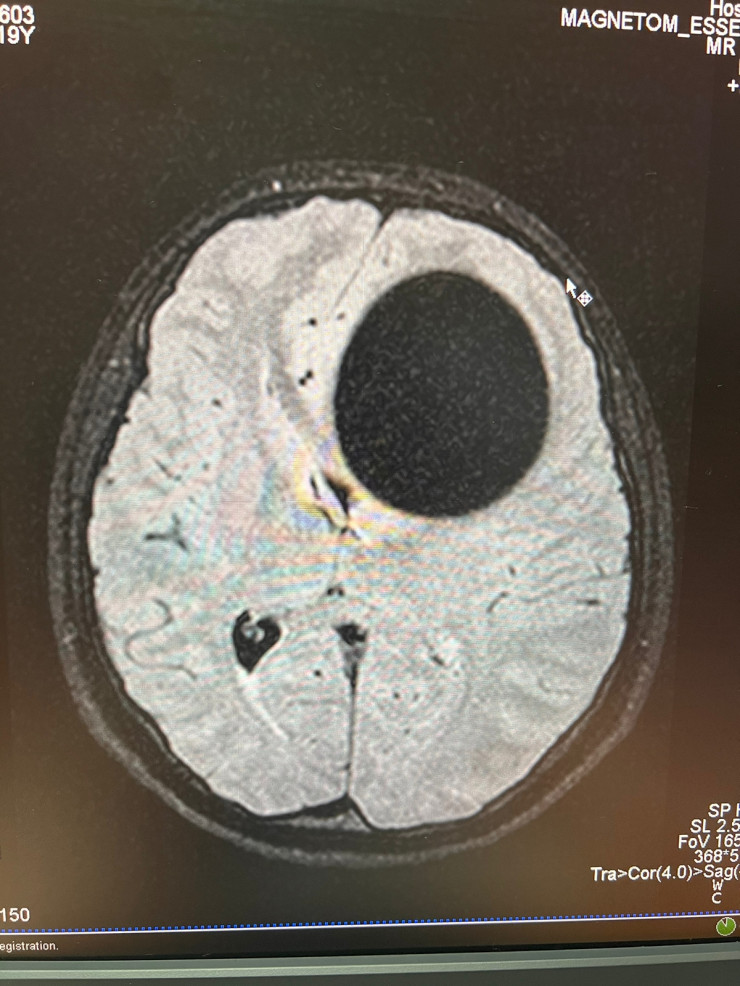

20-летняя пациентка поступила 17 января к невропатологам больницы скорой медицинской помощи (БСМП) Семея. Сначала у нее подозревали инсульт, однако на компьютерной томографии в головном мозге была выявлена огромная киста диаметром 5,5 сантиметра.

Эхинококковая киста диаметром 5,5 сантиметра. Материал предоставлен общественным объединением KAZNEURO

Так выглядит эхинококковая киста головного мозга. Материал предоставлен общественным объединением KAZNEURO